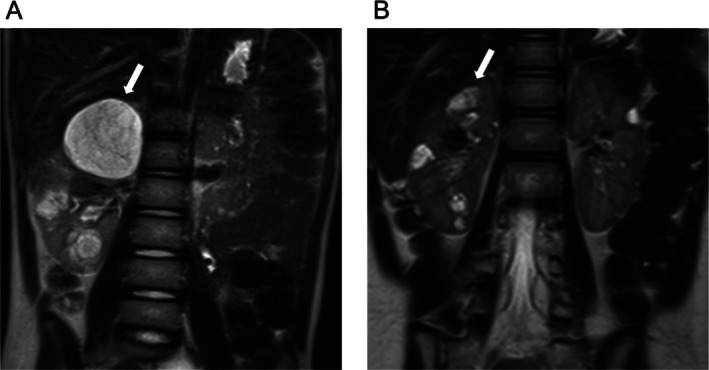

Renal angiomyolipomas (AMLs) are a common renal manifestation in tuberous sclerosis complex (TSC), occurring in 50%-85% of cases. Even in asymptomatic individuals, treatment is often initiated based on AML size, with mTOR inhibitors being the primary medical therapy. AMLs tend to enlarge with age, and treatment during school age is rare. Secondary AML shrinkage in paediatric TSC patients has been reported who received everolimus for subependymal giant cell astrocytomas (SEGA) or epilepsy, but studies on its direct use for AMLs in paediatric cases remain limited. A 9-year-old girl born to a mother with TSC was diagnosed at birth due to cardiac rhabdomyomas, cortical tubers, and Shagreen patches. At the age of 4, ultrasound detected multiple AMLs in both kidneys, with the largest lesions measuring 2.3 cm in the right kidney and 1.6 cm in the left. By the age of 7, MRI showed further growth to 4.8 cm. Despite the absence of symptoms, the risk of haemorrhage led to treatment initiation. Everolimus was started at 1.0 mg/day (1.3 mg/m2/day), significantly lower than the standard 4.5 mg/m2/day. Trough levels remained below the target range, yet AMLs showed a shrinking tendency, with MRI at age 9 revealing a reduction in the largest AML to 2.4 cm. Stomatitis occurred intermittently, but no serious adverse effects were observed. This case suggests that low-dose everolimus can effectively reduce AML size while minimising adverse effects, highlighting its potential as a treatment option for AMLs in paediatric TSC patients.